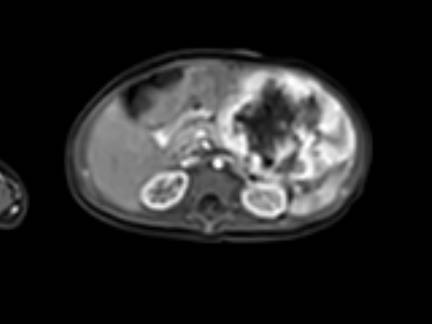

Hình ảnh MRI của một bé gái chín tháng tuổi có khối u ở bụng trái. MRI cho thấy khối u tuyến thượng thận trái, một phần đặc, một phần nang. Có nhiều di căn gan.

Khối u đã được sinh thiết. Có tình trạng chảy máu liên tục qua kim dẫn đường. Vào cuối thủ thuật, hai nút bọt gelatin đã được đặt vào (các dải tăng âm (mũi tên)).